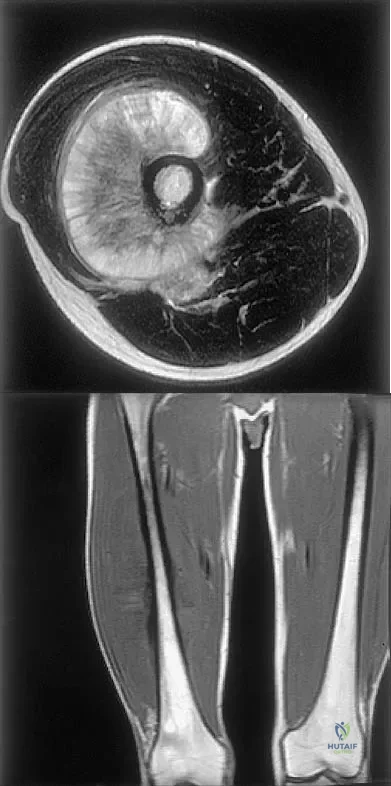

Figures 31a and 31b show the T1- and T2-weighted MRI scans of a patient's knee joint. What is the most likely diagnosis?

Explanation

Figures 35a and 35b show the axial T2-weighted and coronal T1-weighted MRI scans of a patient who has enlargement of the right thigh. What is the most likely diagnosis?

Explanation